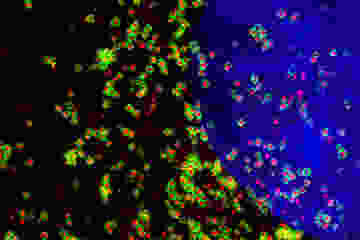

Image: Julia Alterman, Dr. Anastasia Khvorova's lab. This image shows direct targeting of siRNA to silence the Huntington’s disease gene, in the brain of a mouse after injection of these siRNA molecules into the cerebrospinal fluid.